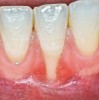

The workshop's group on periodontal soft-tissue root coverage procedures evaluated the predictability of root coverage procedures for single- and multiple-tooth Miller Class I and II10 periodontal recession defects. The workshop concluded that predictable root coverage was possible for Miller Class I and II recession involving a single tooth. When compared with the use of acellular dermal matrix graft (ADMG) (donor tissue) or EMD (porcine origin), procedures using a subepithelial connective tissue graft (SCTG) harvested from the patient's palate provided the best root coverage outcomes in conjunction with a coronally advanced flap.11 As alternatives to autogenous donor tissue, the workshop found strong evidence to support the use of an ADMG or EMD in conjunction with a coronally advanced flap and limited evidence to support the use of platelet-derived growth factor and xenogeneic collagen matrix.11 In addition, root coverage procedures were found to be effective for Miller Class I and II recession defects affecting multiple teeth, although the evidence is limited.11 Figure 1 and Figure 2 show the pretreatment and 1-year postoperative views of a soft-tissue root coverage treatment with SCTG and EMD that used a coronally advanced flap and a tunneling procedure. Figure 3 and Figure 4 depict the pretreatment and 3-year postoperative views of a root coverage procedure with ADMG and EMD that used a coronally advanced flap and a tunneling procedure (this patient was noncompliant following surgery and did not return to the office until the 3-year postoperative appointment).

(1.) Pretreatment view of single incisor with gingival recession exposing the root.

Figure 1

(3.) Pretreatment view of recession affecting multiple maxillary teeth.

Figure 3